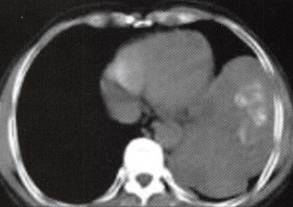

图1胸膜孤立性纤维瘤

A

B

C

D

A.B.CT平扫示左中下胸巨大肿块,宽基底与胸壁相连,内见斑片状钙化;

C~F.CT增强扫描肿块内缘肺门侧见一血管蒂样结构与纵隔相连,中度不均匀强化,内见匍行、紊乱的血管影,肿块中度均匀强化;